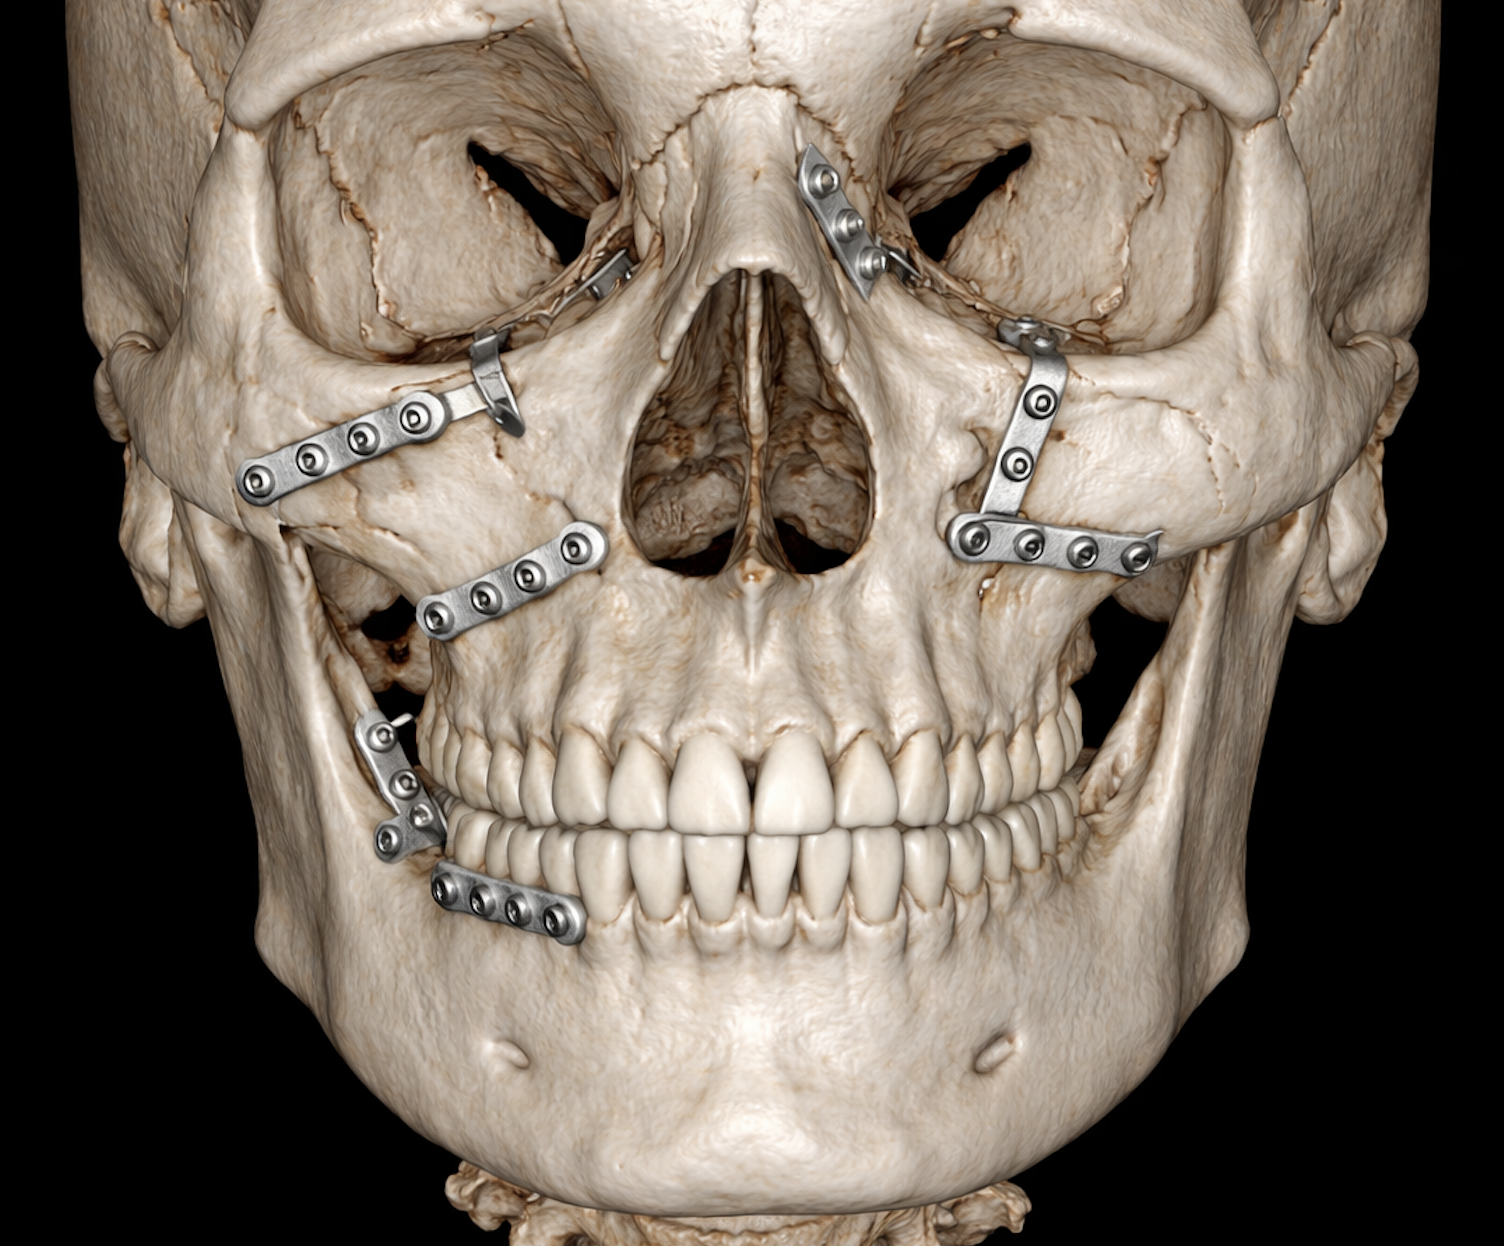

Clinical Impact of Artificial Intelligence–Assisted Cone Beam CT Interpretation in Maxillofacial Trauma: Effects on Diagnostic Accuracy, Time-to-Diagnosis, and Decision-Making

This study demonstrates that AI-assisted interpretation of DVT images enables near-perfect detection of maxillofacial fractures while significantly reducing diagnostic time. The benefit is most pronounced for junior surgeons, highlighting the clinical value of AI as a decision-support tool in emergency maxillofacial trauma care.

This multicenter study externally validated an artificial intelligence (AI) system for detecting maxillofacial fractures on cone-beam CT (DVT) scans. The AI demonstrated high sensitivity, specificity, and overall accuracy across both a tertiary trauma clinic in Zurich and an independent maxillofacial practice in Munich. Performance was comparable to senior clinicians, significantly faster than human interpretation, and robust across different clinical settings.

Artificial Intelligence–Assisted Decision Support in Emergency Maxillofacial Trauma Imaging: Development and Validation of a CBCT-Based Clinical Decision Algorithm

This study developed and validated an AI-assisted, CBCT-based clinical decision support algorithm for emergency maxillofacial trauma that translates automated fracture detection into standardized management recommendations. The algorithm showed high concordance with expert consensus, reduced decision variability and time, and safely supported clinical decision-making across different institutional settings.